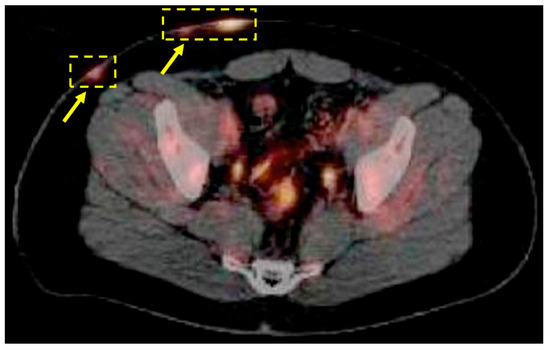

| Kim 2020 [36] | 62-year-old man had recurrent abscesses in his bilateral buttocks for 3 years | FDG-PET/CT | For three years, a 62-year-old man experienced recurring abscesses in both his buttocks. After seeking medical attention, he was diagnosed with hidradenitis suppurativa, and subsequently underwent a pelvic CT scan which revealed the presence of a 10 cm abscess in the subcutaneous tissue. Further investigation was carried out using a PET scan to ascertain the origin and condition, which indicated an increase in FDG uptake. This uptake was attributed to both hidradenitis suppurativa and malignancy. | Yes |